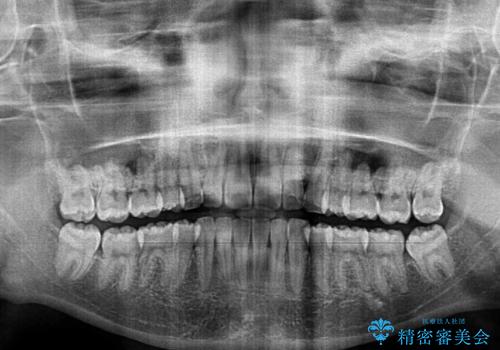

- 上下の出っ歯を気にして来院された患者様です。

口元を積極的に引っ込めるために、上下左右の第一小臼歯を4本抜歯することとしました。

途中で来院されない時期があったため、期間が長引き、更には磨き残しが多かったことで虫歯が多く発現してしまいました。

しっかりと通院するようになってからは順調に治療が進み、横顔の印象が変わるほどスッキリとした口元となりました。